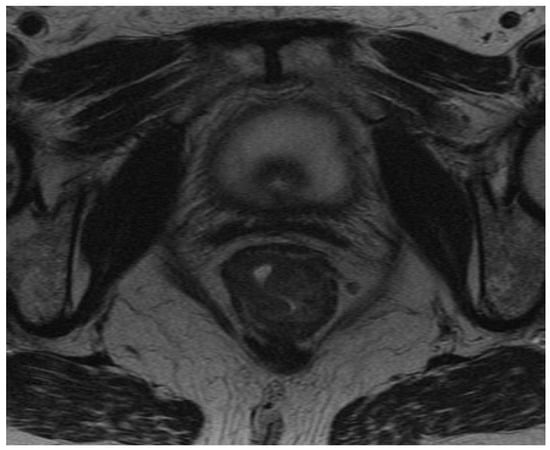

2.2. Assessment of Status of EMVI

- Inoue, A.; Sheedy, S.P.; Heiken, J.P.; Mohammadinejad, P.; Graham, R.P.; Lee, H.E.; Kelley, S.R.; Hansel, S.L.; Bruining, D.H.; Fidler, J.L.; et al. MRI-detected extramural venous invasion of rectal cancer: Multimodality performance and implications at baseline imaging and after neoadjuvant therapy. Insights Imaging 2021, 12, 110. [Google Scholar] [CrossRef]